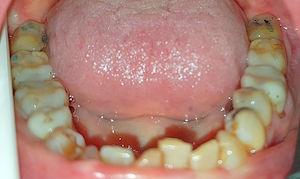

Bei kräftigem Knirschen werden pro 10 Jahre die Milchzähne etwa 3 mm und die bleibenden Zähne etwa 1 mm abgeschliffen.

Bei dieser Patientin hat der Bruxismus etwa 1 Zahn und 1 mm Zahnsubstanz pro 10 Jahre gekostet.

Die Füllungen und Wurzelbehandlungen haben etwa 10'000 CHF und

die Kronen, Brücken und das Implantat etwa 20'000 CHF gekostet.

Diese Schäden sind mehrheitlich nicht wegen Karies, sondern wegen dem Bruxismus entstanden.